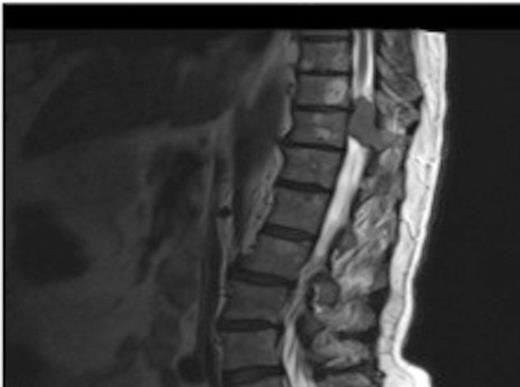

MRI showing the extra-dural tumour and extension into the soft tissue of the back

A one-year history of lower back pain, which was initially thought to be due to his liver metastasis, was investigated further with a full spine MRI scan. The scan revealed a large T10-11 extra-dural tumour with erosion of the T12 pedicle and extension into the soft tissue of the back. As a result of this discovery, the patient was referred for radiotherapy. Prior to commencement of this the oncologist requested a neurosurgical opinion from us.